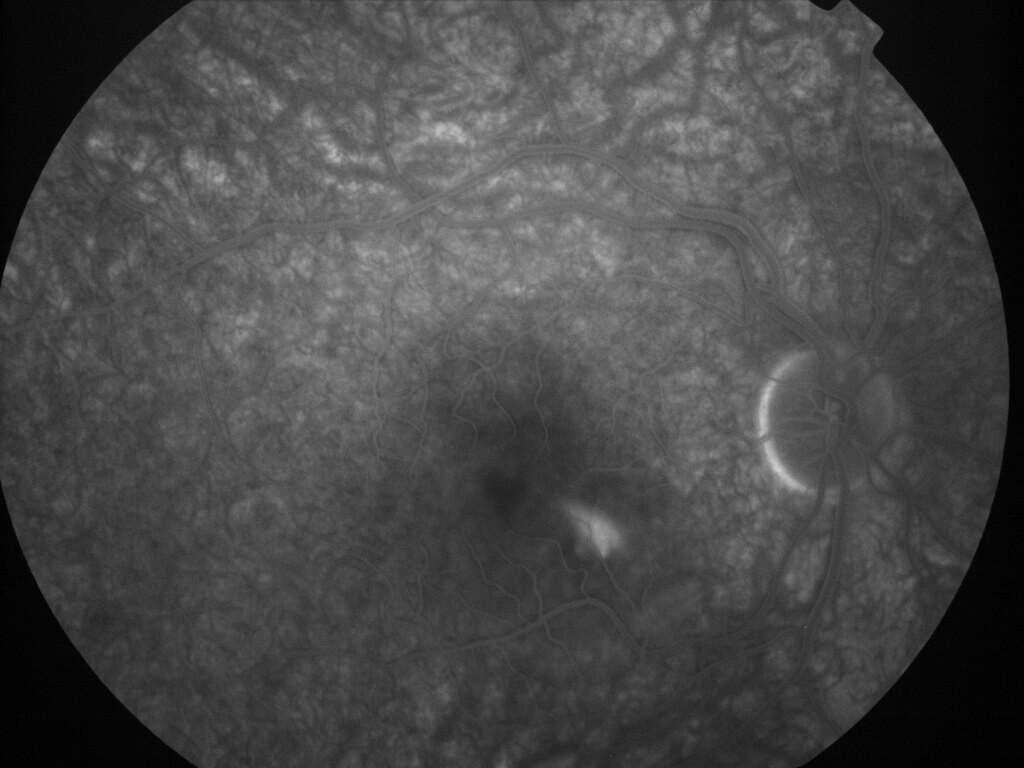

CHORIORETINOPATHIE SEREUSE CENTRALE